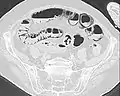

Pneumatosis intestinalis in computed tomography with intestinal ischemia. Lung window for better representation of the gas deposits in the intestinal walls.